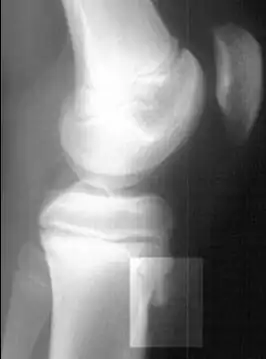

Radiografía lateral de la rodilla demostrando fragmentación del tubérculo tibial, con tejido sobreabundante | ||

Una radiografía de hueso puede ser normal o puede mostrar inflamación o daño a la espina tibial. Las radiografías se usan muy poco, a menos que el médico quiera descartar otras causas del dolor.